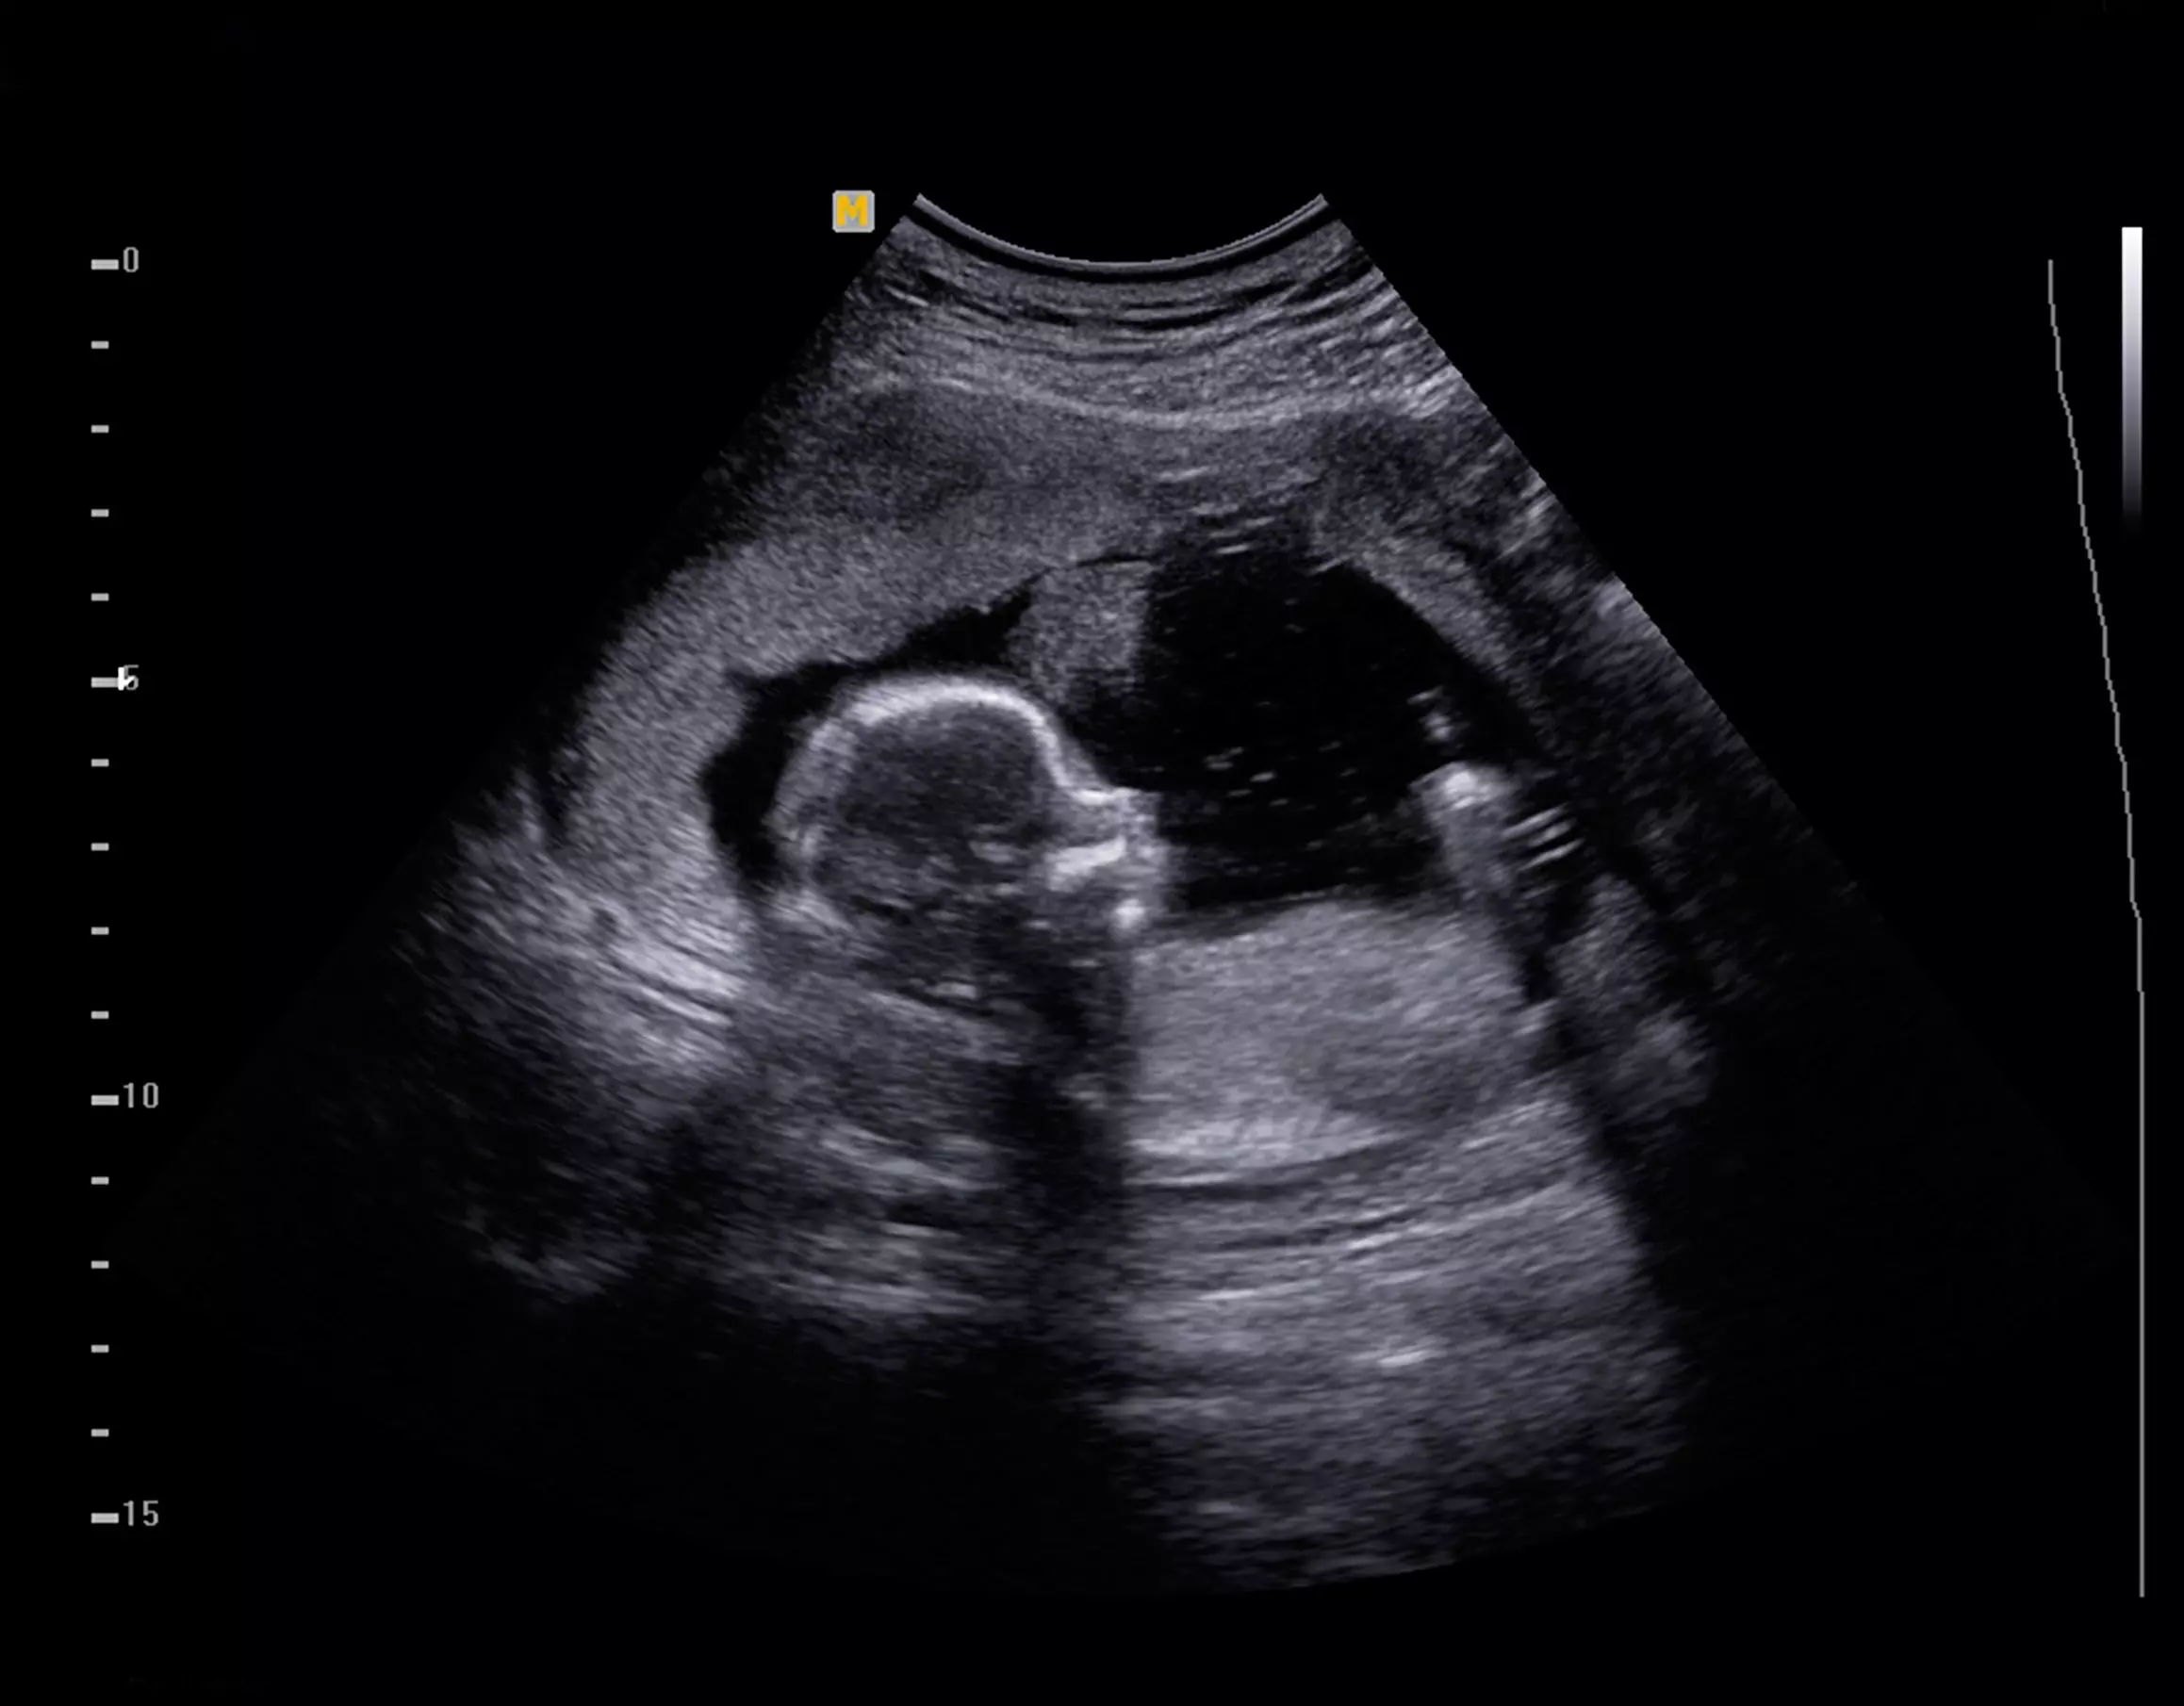

Sure enough, the ob/gyn office confirmed the pregnancy, in all its glory, in the ultrasound image that appeared on the screen. The mother was overcome by emotion at the portrait of personhood before her, very early in the first trimester of pregnancy.

She was also enamored by the heartbeat that was clearly detectable in the preborn baby’s first six weeks of life in the womb.

As a viewer, I felt pure joy at this scene—a mother and father seeing their beloved child for the first time. The image was to be the first in the baby’s scrapbook.

But in the end, the ultrasound image carries with it a dignity and grace which cannot be denied. Life bursts from the screen with all its possibility and promise.